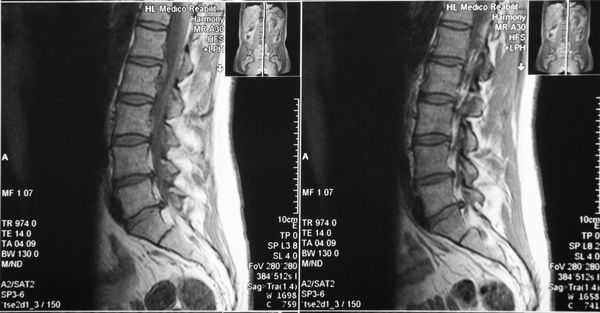

Функциональная спондилография поясничного отдела от 12.02.2019: остеохондроз II степени; спондилоартроз; нестабильность сегментов на уровне L4-L5 и L5-S1; ретролистез — смещение L5 позвонка назад — I степени. Электронейромиография (ЭНМГ) от 12.02.2019: малоберцовые нервы в норме с обеих сторон; признаки заинтересованности корешков L4-S1 справа. Мультиспиральная компьютерная томография (МСКТ) ПКОП от 13.02.2019: КТ-картина дегенеративно-дистрофических изменений поясничного отдела позвоночника; большая задняя срединная грыжа межпозвонкового диска на уровне L4-L5 позвонков с абсолютным стенозом спинального канала; задние диффузные протрузии дисков L5-S1 и умеренная протрузия уровня L2-L3. МРТ ПКОП от 14.02.2019: МР-картина дегенеративно-дистрофических изменений сегментов ПКОП; задняя медианная экструзия (выбухание) диска L4-L5 с признаками компрессии корешков конского хвоста и вторичного дурального стеноза на уровне L4-L5 на 2/3; протрузии дисков L2-L3 и L5-S1; ретролистез L5 I степени.